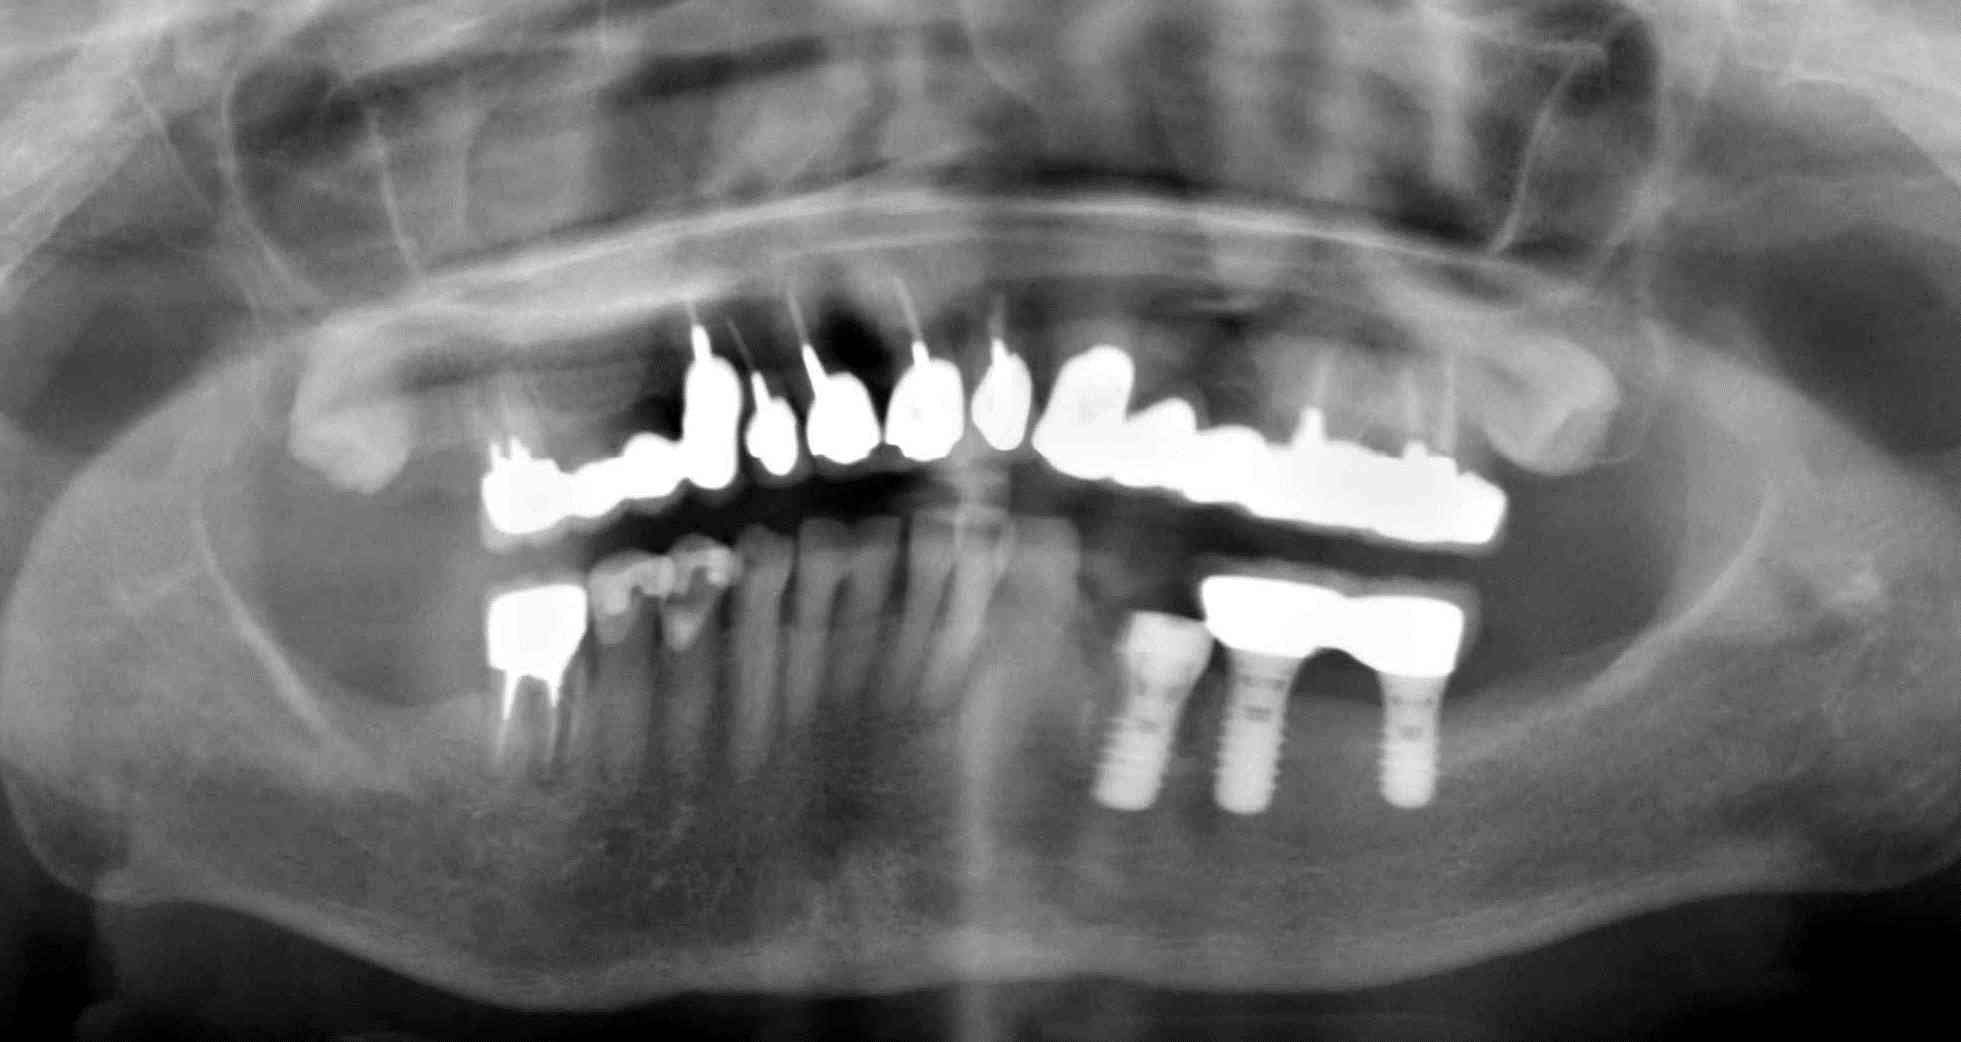

術後のパノラマです。

今日のオペは、下顎両側6番部位の成熟側に1本ずつのサイブロンインプラントを埋入しました。

骨質はクラス4で海綿骨がほとんどありませんでしたので、皮質骨でしっかり固定を撮る必要があるケースです。

右下は、骨幅が狭く裂開が生じました。